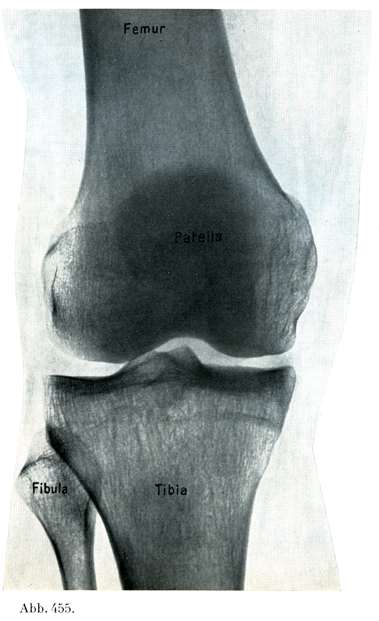

[図455] 膝関節 生体の右膝のレントゲン写真. 前方から後方へ照射(3/4)